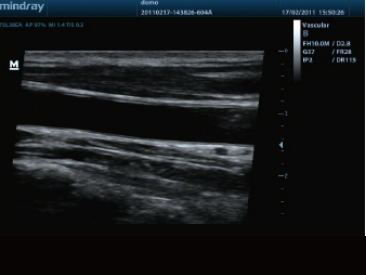

先进的超声成像技术

高端超声技术平台的引进,以及先进的超声成像技术的应用,给DP-50的二维图像质量带来了突破性的提升,大大的增强了超声医生的临床诊断信心。